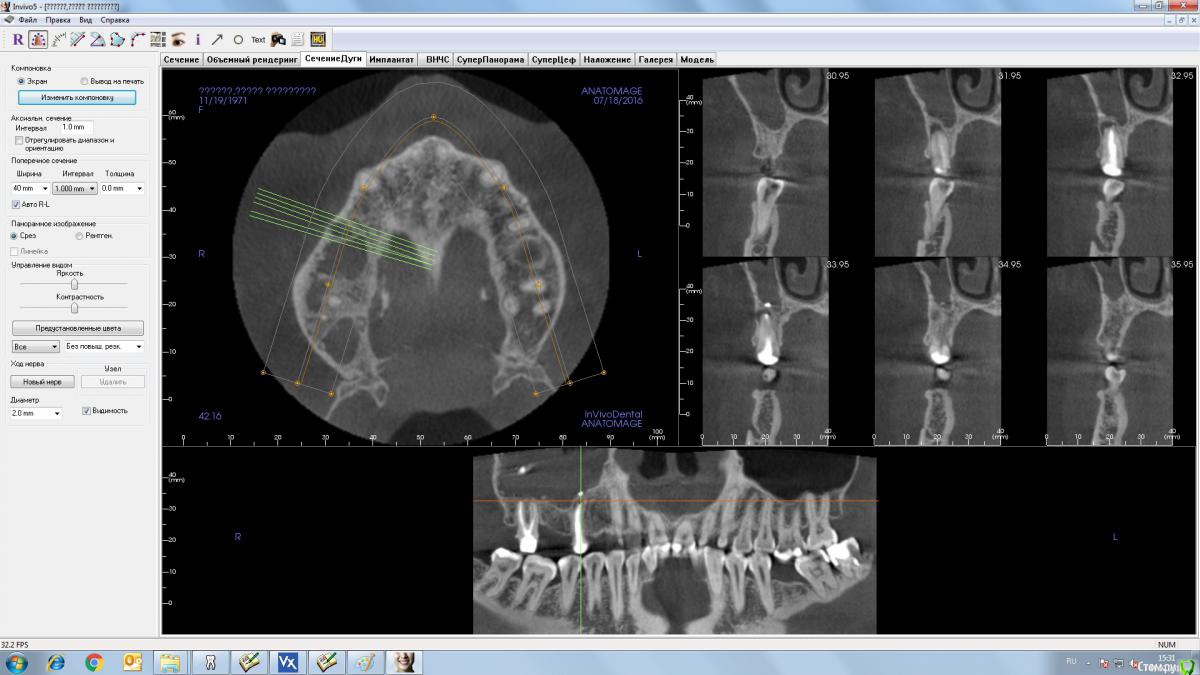

Andrey Shiryaev Опубликовано 19 июля, 2016 Поделиться Опубликовано 19 июля, 2016 (изменено) Уважаемые коллеги, хотел бы получить совет и ваше мнение, как на данную ситуацию. Пациент изначально отказался от ортодонтического лечения. По плану:1. вариантвизит ЛОР, ( какие ждут пациента манипуляции???)после чего удаление 15, 17 зубов, возможно закрытие ороантрального соустья.Через 6 месяцев имплантация и далее все по плану. 2 вариант.Была мысль поставить 14, 16 (с закрытым синусом) импланты, провизорную конструкцию, через 3 недели удаление 15, 17.Через 6 месяцев установка 15,17 импланты. Смущает только возможность обострения 15 и 17 зубов после имплантации 14,16.Так как я относительно молодой хирург-имплантолог, прошу совета, может есть какие-то другие варианты.И хотелось бы узнать, если мы будем двигаться по первому плану, то какую конструкцию в качестве временной можно использовать? Точнее лучше использовать. Изменено 19 июля, 2016 пользователем Andrey Shiryaev Ссылка на комментарий

Andrey Shiryaev Опубликовано 19 июля, 2016 Автор Поделиться Опубликовано 19 июля, 2016 14 залезет без пробелем, а вот 16 там около 7 мм, т.е. Как минимум закрытый сделать нужно будет. Ссылка на комментарий